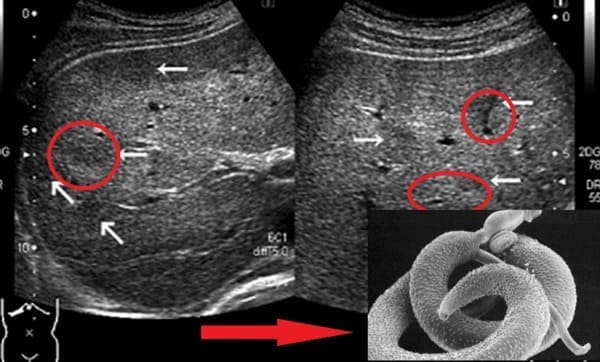

A paraziták "útjai" a bél lumenében

Leggyakrabban a belekben kezdődik. A paraziták a szájon keresztül jutnak be a tápcsatornába, és problémát okoznak. Később más szervekbe is bejuthatnak, kiterjedt elváltozásokat okozva. Nézze meg az alábbi képeket.